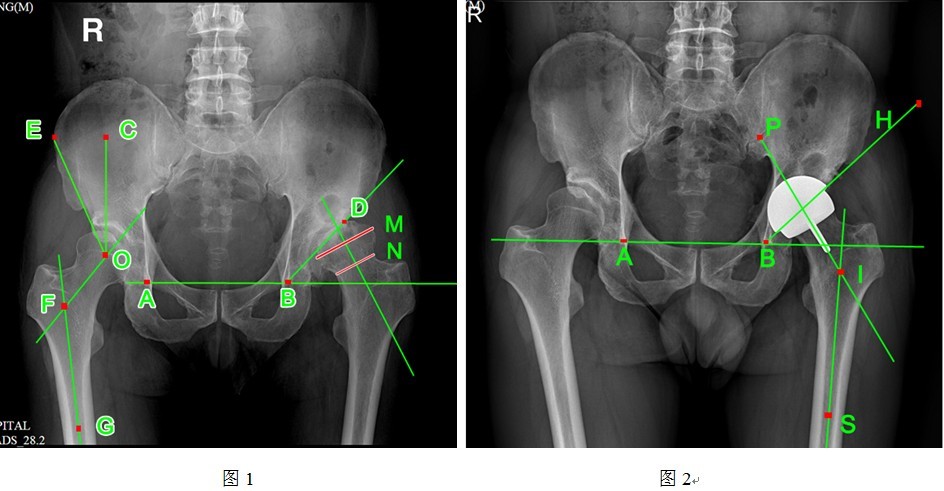

二、影像学测量

术前、术后均拍摄标准骨盆正位片,单侧髋关节正侧位片,摄片时双足内旋15度。通过南方医科大学研发的PACS系统测量术前髋臼Sharp角与术后髋臼外展角、术前头颈比例、术前颈干角与术后柄干角、术前CE角以及术后髋臼杯假体外露情况(具体测量方法详见图1~2)。按照髋臼3区和股骨柄正位7区、侧位7区描述透亮带。

①髋臼角:AB与BD的夹角(A 、B为双侧泪滴投影点,D为髋臼外上缘投影点);

②CE角:CO和OE的夹角(O为股骨头中心点,CO为经过O点的垂线,OE为自股骨头中线点至髋臼外上缘的连线);

③颈干角:GF与OF的夹角(GF为股骨轴线,OF为股骨颈轴线);

④头颈比:M/N的数值(M线为股骨头直径,N线为股骨颈直径);

⑤髋臼外展角:AB和BH的夹角(AB为双侧泪滴连线,BH为髋臼边缘投影);

⑥柄干角:PI与SI的夹角(PI为股骨头中心杆轴线,SI为股骨轴线)。